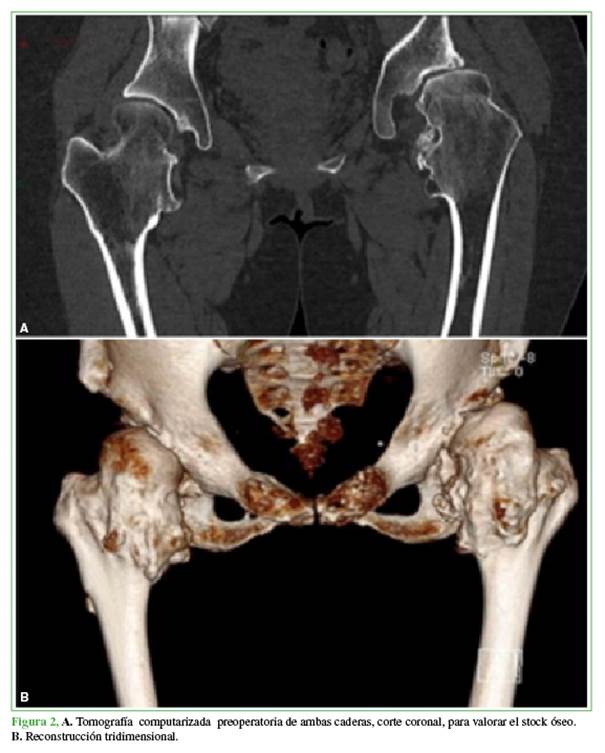

Mujer de 42 años de edad, con antecedentes familiares de EMH en su línea paterna que consultó, por primera vez, por coxalgia izquierda de dos años de evolución. Refería un dolor intenso con la carga de peso y limitación de las actividades cotidianas. La movilidad de la cadera era de 120º de flexión, 30º de abducción y limitación de las rotaciones. El puntaje de cadera de Harris9 era de 75. En la radiografía de pelvis, se observó una displasia bilateral de cadera con subluxación de la cabeza femoral y protuberancias óseas (exostosis) en ambos trocánteres menores hacia la cabeza femoral (Figura 1). La cadera izquierda tenía un ángulo cervico-diafisario de 165º, incongruencia acetabular y signos artrósicos que eran más evidentes en la tomografía computarizada (Figura 2). En las radiografías de rodillas y tobillos, se visualizaban las múltiples exostosis y una anquilosis tibio-peronea (Figura 3).